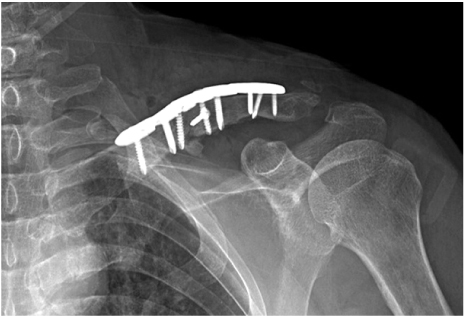

The surgery of the clavicle was performed by a shoulder specialist at our hospital. An incision was made along the clavicular axis on the previous operation scar. The previous plate and screws leaving out a lag screw were removed. Fibrous and granulated tissue of the nonunion site was excised and the ends of each fragment were prepared with curettage. Fracture reduction and fixation were achieved with a longer locking compression plate. The autogenous cancellous bone graft from the left femoral head was packed in the fracture gap after total hip arthroplasty. The wound was closed in a layered fashion after confirmation of satisfactory fracture reduction and implant position with an image intensifier (Fig. 2).

Postoperative neurovascular status was intact, and we found no abnormal findings until postoperative day 3. On postoperative day 4, the patient presented with numbness in the left hand and decreased strength. A grade 1/5 in thumb extension and flexion, wrist extension, and finger extension, flexion, and abduction was found in addition to a grade 3/5 in wrist flexion and elbow flexion and extension. A haematoma formation at the operation site was suspected because of the acute onset of symptoms on postoperative day 4. On postoperative day 5, an ultrasound was performed for evaluation of a possible haematoma, but no definite mass or haematoma was found around the clavicle. On postoperative day 6, diffusion magnetic resonance imaging (MRI) was performed to evaluate for possible acute stroke, but there was no evidence of acute infraction. Additionally, on postoperative day 6, cervical spine MRI was performed to evaluate the cervical spine. Cervical spine MRI demonstrated a fibrotic mass lesion around a small bony fragment inferior to the clavicle. This lesion was compressing the adjacent brachial plexus causing signal changes within the brachial plexus (Fig. 3). Based on the MRI findings, we removed the implant and made a superior angulation to decompress the brachial plexus. There was no haematoma intraoperatively, and we left grafted bone. We put a Velpeau sling on the patient's left shoulder after surgery (Fig. 4).

(A) Immediate postoperative radiograph after the second surgery. Callus bridging is seen on the 3-month follow-up radiograph (B) and consolidation processing on the 6-month follow-up radiograph (C).